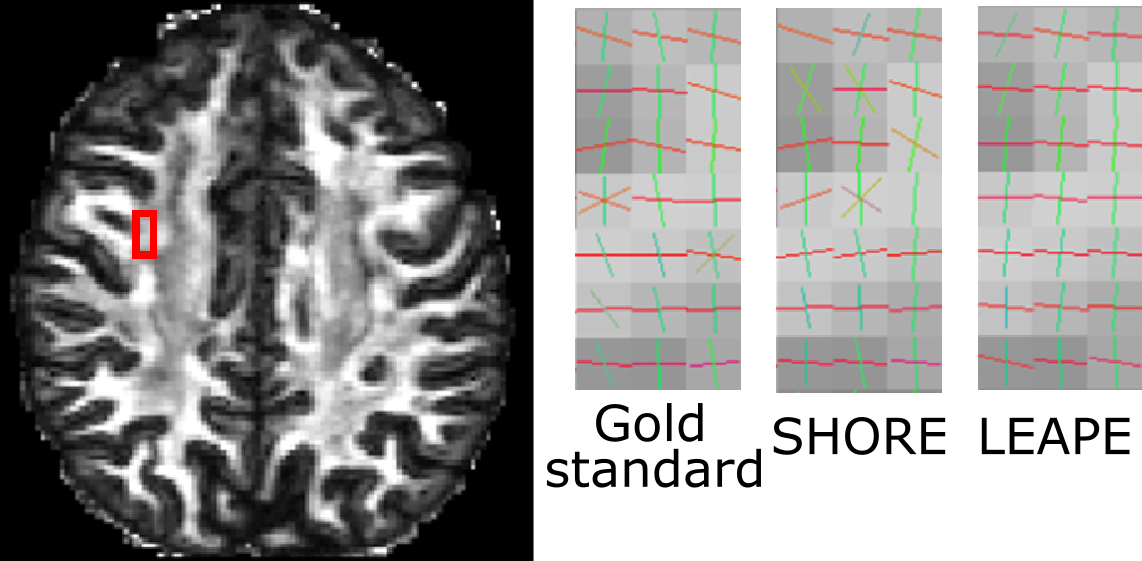

Next, we evaluated the FOs extracted from the EAP. A qualitative comparison is made in Fig. 5, where we focus on a region where the corpus callosum (CC) and superior longitudinal fasciculus (SLF) cross. We can see that the LEAPE result resembles the gold standard, and LEAPE better resolves crossing FOs and produces smoother FOs than SHORE. The LEAPE FOs are even smoother than the gold standard in some cases. We also computed the average FO disagreement with the gold standard in the white matter for SHORE and LEAPE (see Fig. 4). Note that if the second MLP in LEAPE is not used for training, the FO errors range from 20superscript2020^{\circ} to 24superscript2424^{\circ} (not shown in Fig. 4), and for every subject the errors are higher (>10%absentpercent10>10\%) than those of SHORE or LEAPE. This indicates the benefit of adding the second MLP. Compared with SHORE, the mean and median of the disagreement of LEAPE are smaller. The difference of disagreement between SHORE and LEAPE is small. This is possibly because for the less complicated FO configurations (for example, noncrossing FOs), which occupy a large proportion of the white matter volume, both SHORE and LEAPE are able to produce good results with 60 diffusion gradients, and the difference like the one shown in Fig. 5 is present at regions with more complex FO configurations.

Refer to caption

Figure 4: Boxplots of the quantitative disagreement between the estimated results (MSD, RTOP, and FOs) and the gold standard for the ten subjects. The means are indicated by the diamonds. Asterisks (***) indicate that the difference between the inaccuracy of LEAPE and SHORE is highly significant (p<0.001𝑝0.001p<0.001) using a paired Student’s t𝑡t-test.

Figure 5: FOs overlaid on the FA map in a region where the CC and SLF cross.